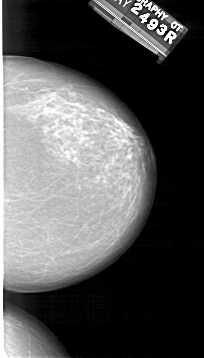

A_1410_1.RIGHT_MLO

RIGHT_CC LINES 5716 PIXELS_PER_LINE 3256 BITS_PER_PIXEL 12 RESOLUTION 43.5 NON_OVERLAY